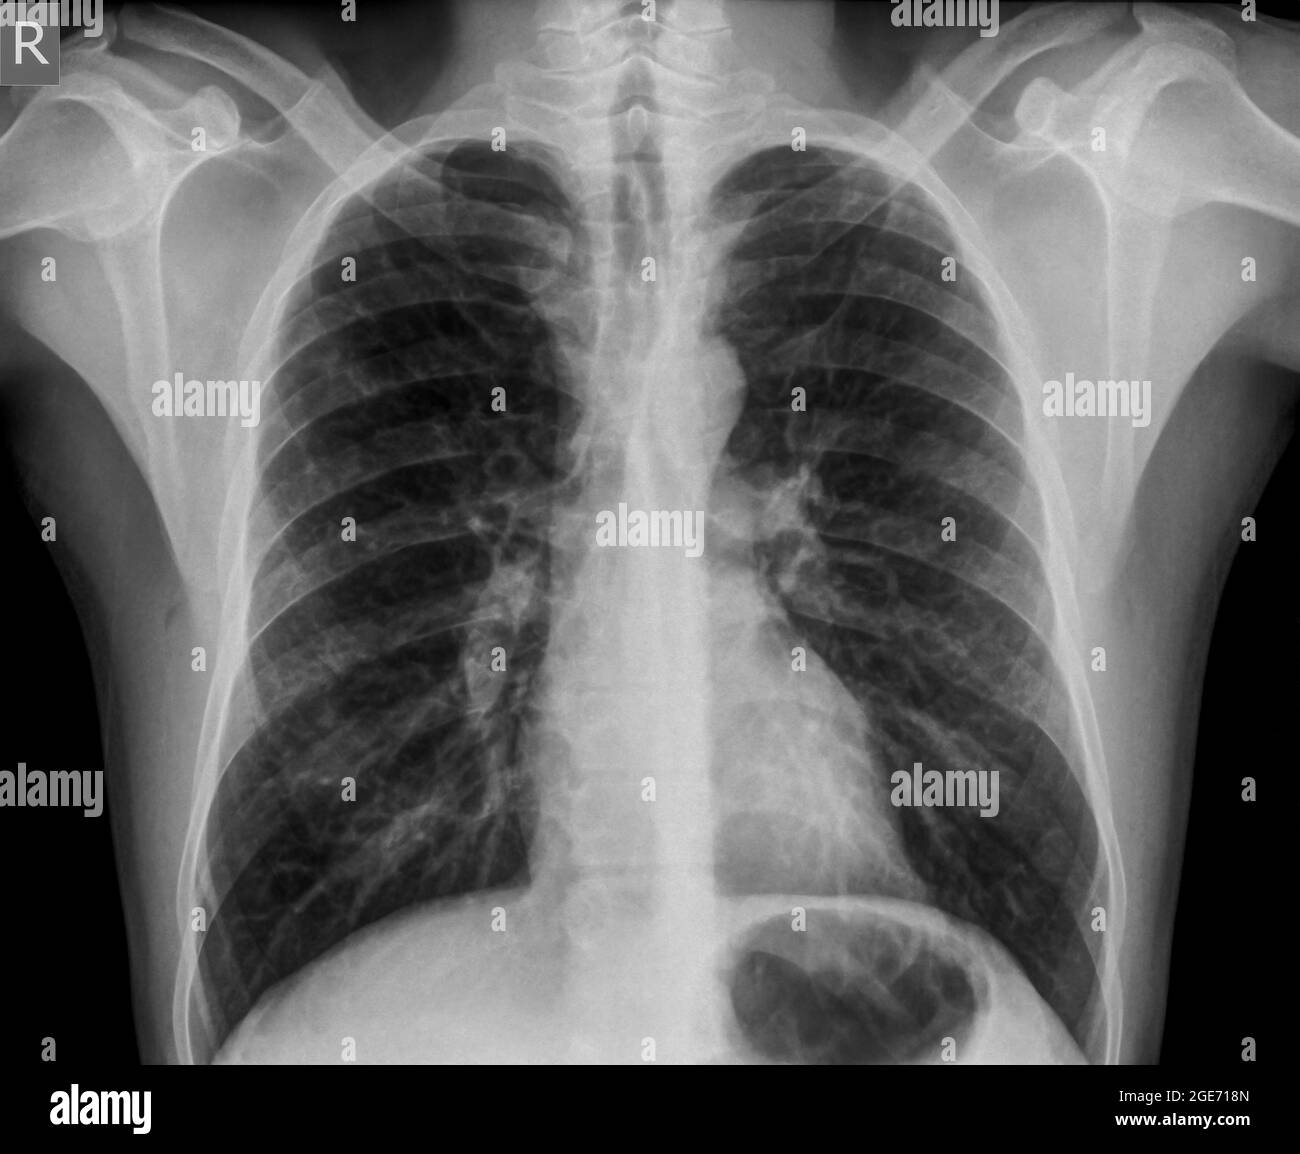

Lista es una colección y muestra de imágenes sobre imagenes de pulmones sanos y enfermos realizada por upup.edu.vn. Además, hay imágenes relacionadas con imagenes de pulmones sanos, imágenes de pulmones sanos, radiografía de pulmones sanos y enfermos, fotos de pulmones sanos, radiografía pulmones sanos y enfermos, rayos x de pulmones sanos y enfermos, pulmon sano y enfermo, pulmón sano y enfermo . Para más información, consulta a continuación.

imagenes de pulmones sanos y enfermos

Posts: imagenes de pulmones sanos y enfermos